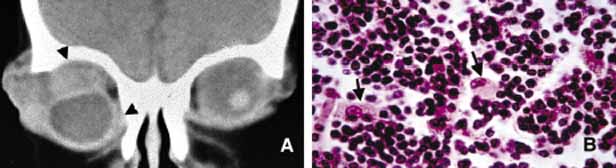

For the sake of simplicity, orbital neoplasia are divided into three major subgroups: primary, secondary and metastatic (Table 4). Further, the primary neoplasms are categorized based on the cell of origin (vascular, neural, etc.), and secondary and metastatic neoplasms are grouped based on the organ of origin (e.g., skin melanoma, breast carcinoma, etc.). Another simple but very important division is performed according to the biologic behavior of neoplasms: benign versus malignant. Further subgrouping of neoplasia is based on the type of tissue that gives origin to tumors: epithelial tissues (adenoma/carcinoma), mesenchymal tissues (benign mesenchymal tumors/sarcomas) and hematopoietic and lymphoid tissues (leukemia/lymphoma).159 Because the orbit contains a large variety of tissues ranging from bone to blood vessels, many tumors develop within the orbit as primary neoplasms (Table 5). In general, carcinomas proliferate as chords and clusters of cells simulating surface and glandular epithelium. Sarcomas, however, proliferate in tightly coherent sheets of cells that are most often fusiform in shape with elongated nuclei. Leukemic and lymphoproliferative lesions have loosely coherent sheets of cells with rounded nuclei and scanty cytoplasms. Histiocytic proliferations such as histiocytoses and necrobiotic xanthogranuloma may also present as proliferative lesions within the orbit. Secondary neoplasia include benign and malignant tumors that invade the orbit by direct extension from the neighboring structures including the globe, brain, nose, and paranasal sinuses, skin, conjunctiva and lacrimal drainage system.

Many metastatic neoplasms originating from other organ systems may find their way to the orbit by hematogenous spread. The most common metastatic malignancies include breast, lung and kidney carcinomas, cutaneous melanoma and rarely sarcomas originating elsewhere in the body.160–162 Tumor-like conditions such as pseudotumors, granulomas, congenital lesions (hamartomas, choriostomas, etc.) that may also invade orbit secondarily are covered elsewhere in this chapter. Both the clinician who evaluates the patient with an orbital space occupying lesion and the pathologist who examines the tissue removed from an orbital mass, must have a working knowledge of the frequency of orbital neoplasms and tumor-like conditions163–166 (Table 4). More commonly encountered acquired orbital neoplasms are detailed. PRIMARY TUMORS Epithelial Neoplasms Primary epithelial neoplasms of the orbit originate from the ductal and acinar epithelium of the lacrimal gland.167,168 The most commonly encountered lacrimal gland tumor is pleomorphic adenoma (benign mixed tumor) (BMT). This neoplasm is known as a “mixed” tumor because it is composed of a mixture of epithelial and stromal elements (Fig. 14). The epithelial elements of the tumor consist of glandular and ductal formations that may develop squamous metaplasia and small keratin filled cysts. The stroma is composed of myxoid tissue that may contain cartilage and bone. In most cases the BMT of the lacrimal gland is multilobulated and surrounded by a fibrous capsule. If additional smaller lobules are present in the vicinity of the main lesion, these satellite nodules are individually encapsulated as well. When malignancy develops within a BMT it is classified according to its predominant histopathologic component as adenocarcinoma within pleomorphic adenoma, adenoid cystic carcinoma, or poorly differentiated carcinoma. Malignant transformation may happen as a rapid growth within an unknown tumor or may take place decades after diagnosis of the BMT.169 Adenoid cystic carcinoma, the most common malignant tumor of the lacrimal gland may also develop de novo. This is a highly malignant neoplasm that can be seen in adolescents and may develop rapid extension into the adjacent structures including the cranium by direct invasion and to the base of the skull by painful perineural invasion.170,171 The histopathologic appearance of adenoid cystic carcinoma may present as several variants including the most common “Swiss cheese” pattern that consists of cribriform clustering of small basophilic tumor cells surounded by thick basement membrane (Fig. 15). Other types including diffuse basaloid, sclerosing, tubular, and comedocarcinoma are known to exist.172 Both benign and malignant tumors of the lacrimal gland present with proptosis and inferior medial displacement of the globe that can readily be demonstrated on CT and MRI studies showing cavitation of the lacrimal fossa in chronic benign lesions and direct invasion of the bony tissues in malignant tumors. Adenocarcinoma developing in BMT (pleomorphic adenocarcinoma, malignant mixed tumor) presents with atypical features within tubular and glandular structures.169 Mucoepidermoid carcinoma of the lacrimal gland consists of diffuse proliferation of atypical squamous cells with abundant vacuolated cytoplasm containing mucin. The clinical course of mucoepidermoid carcinoma is chronic with a relatively favorable prognosis.173,174 Other than true neoplasms, cystic dilatation of the lacrimal gland ductules that is known as dacryops and ectopic lacrimal gland tissue presenting in areas away from the anatomic site of the gland also present as space occupying lesions in the lacrimal fossa.175–177 Mesenchymal Neoplasms The traditional grouping of the primary vascular tumors in the orbit include capillary and cavernous hemangiomas, lymphangioma and arteriovenous malformations. The current thinking is that these lesions represent hamartomas that are made of different tissue components and may be better defined as “vascular hamartomatous lesions.”178 Histopathologic examination of these tumors often reveals mixtures of above listed tissue elements, the symptomatology, clinical course and response to treatment depends on the predominating histopathology. For example, if capillary hemangioma is the dominating element of a vascular tumor it is most often apparent at birth or within the first year, occurs in the anterior orbit and gradually regresses without any treatment. 179 Approximately 70% of capillary hemangiomas regress completely by 7 years of age. Patients with orbital capillary hemangioma may also have similar lesions in other organs. If systemic involvement is extensive, secondary thrombocytopenia known as Kasabach-Merritt syndrome develops. These lesions grossly appear as bright red, strawberry-like masses; histopathologically they are made of sheets of vascular endothelial cells with small lumen formations. Basement membranes surrounding these cells can be clearly identified with a reticulin stain. The predominating cell of the lesion is confirmed to be endothelial cell, by the positive staining for factor VIII, CD31 and CD34. The identification of an intracytoplasmic organelle known as Wiebel-Palade body by transmission electron microscopy also confirms the nature of the tumor cell as vascular endothelium (Fig. 16). For adnexal and orbital capillary hemangioma the treatment options include observation, intralesional and systemic corticosteroids, systemic interferon and in some cases surgical excision and radiation therapy.180–182 Another type of orbital tumor that originates from blood vessels is hemangiopericytoma, which is a pseudoencapsulated spindle cell tumor composed of vascular pericytes183 (Fig. 17). In these tumors the reticulin network surround the individual tumor cells in hemangiopericytoma as opposed to small groups of epithelial cells in capillary hemangioma. In hemangiopericytoma the tumor cells stain positively with factor VIII, CD34, and occasionally vimentin. The histopathologic pattern that may present considerable pleomorphism with increased number of mitotic figures may vary from one zone to the other. The degree of pleomorphism and high number of mitotic figures are not clear cut indications of malignancy; as a matter of fact, the biological behavior of this tumor cannot be determined based on its histopathologic appearance. Metastatases after many years have been described.184 The best treatment for hemangiopericytoma is surgical excision. Cavernous hemangioma is another benign vascular tumor that occurs in adults, usually as a solitary, unilateral lesion, but multiple tumors have been described.185,186 Unlike capillary hemangioma it is not associated with other lesions elsewhere in the body. It is usually located within the muscle cone but may also be seen in extraconal locations and presents with slowly progressive proptosis without too much extraocular motility disturbance (Fig. 18). Gross appearance of cavernous hemangioma is a well encapsulated reddish purple lesion with a sponge-like consistency on its cut surface. Histopathologically, it consists of dilated vascular channels lined by endothelium and smooth muscle and intervening fibrous stroma. The endothelial cells are held together by tight junctions and display basement membrane reduction. Clinical differential diagnosis of cavernous hemangioma on imaging include fibrous histiocytoma, hemangiopericytoma, schwannoma and metastatic tumors.187 Surgical removal of the tumor is the treatment of choice. Another lesion of this category that presents with large cavern formations surrounded by different amounts of fibrous tissue is lymphangioma.188–190 Unlike cavernous hemangioma, however, the space formations in this lesion are not lined by endothelial cells and do not contain vascular smooth muscle; the spaces are lined by flat mesothelial-like cells (Fig. 19). Spontaneous bleeding may take place within these cystic spaces resulting in “chocolate” cysts. In one-third of the cases, lymphoid follicles with germinal centers may be present in the intervening fibrous stroma and some tumors with abundant lymphoid tissue may respond to systemic steroid treatment. Because of the infiltrating nature of this tumor, surgery is not an early option of management; these lesions should be managed conservatively.190 Orbital varix is another orbital vascular lesion that develops as a distention of a venous channel leading to stagnant blood flow resulting in thrombus formation.191 Orbital varices are divided into primary lesions, confined to the orbit and secondary lesions associated with intraorbital and intracranial arteriovenous malformations.54 Vascular hamartomatous lesions may contain arteriovenous malformations with or without abnormal communication between arterial and venous vasculature. These lesions should not be confused with carotid cavernous and dural cavernous fistulas, which affect the orbit secondarily.192 If one clinically suspects an A-V malformation component in an orbital vascular lesion, CT angiogram and arterial and venous angiograms should be used to rule out the connection of the lesion to systemic circulation.193 Color Doppler flow imaging has also been used to examine these tumors. In addition to the above detailed vascular tumors, angiosarcoma, Kaposi sarcoma, intravascular papillary endothelial hyperplasia (IPEH), vascular leiomyoma and angiolymphoid hyperplasia with eosinophilia (Kimura disease), can rarely be encountered in the orbit.194–198 In this chapter, neural neoplasms are covered under two major groups: tumors originating from central nervous system (CNS) tissues, and tumors originating from peripheral nerves. The two most commonly encountered tumors of the optic nerve that involve the orbit are optic nerve glioma and optic nerve meningioma.200 Optic nerve glioma (ONG) is primarily a tumor of childhood.201,202 When it presents in adults a more malignant glioma should be suspected.203 ONG is associated with neurofibromatosis type I (NF-I) with one or both optic nerves involved in approximately 25% of the cases.204 Some authors suggest that patients with NF-I may have a favorable prognosis. In general, the more anterior the glioma, the more favorable the prognosis.205 These tumors produce painless progressive visual loss and proptosis and ophthalmoplegia.206 Optic disc swelling and atrophy is generally present and rarely optociliary shunt vessels may develop.207 Neurofibromatosis (NF) is subdivided into types I and II. It is an autosomal dominant multisystem disease characterized by multiple tumors and developmental abnormalities.208,209 Neurofibromatosis type I presents with numerous ocular adnexal and orbital manifestations including optic nerve and chiasm gliomas and optic nerve sheath meningioma (Fig. 20). Histopathologically ONG is a low-grade pilocytic astrocytoma.210,211 The tumor is composed of proliferating fibrillary astrocytes that may show different degrees of pleomorphism and vascular proliferation (Fig. 21). The axonal component of the nerve is not involved with the neoplastic process during the early stages of the disease. Mitotic figures and necrosis are associated with malignant transformation into higher grades. These tumors show pleomorphic cellular changes, with increased mitotic rate and necrosis. Long standing ONG (”ancient” glioma) may develop degenerative changes including dilated processes of glial cells (Rosenthal fibers) and hyalinization.200 The diagnosis of these tumors has significantly improved with the advances of neural imaging, particularly with MRI and the role of biopsy in the management ONG has become more or less obsolete.212 In unusual cases in which there is rapid tumor enlargement accompanied by visual loss, biopsy may reveal useful information to differentiate between ONG and meningioma and may help in documenting the presence of a malignant glioma. Interpretation of the biopsy sample may be difficult because of the infiltration of the subarachnoid space with pilocytic astrocytes that are similar in appearance to meningeal fibroblasts.213 Another pitfall that should be remembered is that the arachnoidal hyperplasia secondary to ONG may be misinterpreted as a primary meningioma.214 The treatment of ONG includes surgical excision if the extension into the cranium is imminent. Radiation and chemotherapy are generally reserved for patients older than age 5 years with worsening of signs and symptoms.215 Meningioma is a slow-growing tumor originating from the meningoendothelial cells of the arachnoidal layer of the optic nerve or the cranial meninges. These tumors may occur primarily in the optic nerve sheath or extend into the orbit secondarily from the cranial cavity.200 The symptoms of optic nerve meningioma (ONM), which typically affects white, middle-aged females, include slowly progressive, painless loss of vision and proptosis. As the disease progresses, there may be disc edema, orbital ciliary shunts, and optic atrophy.216 Histopathologically meningioma shows varying patterns of meningoendothelial proliferation including sheets of polygonal cells, mixed proliferation of elongated meningoendothelial cells with fibroblasts, and the psammomatous type in which the meningoendothelial cells form eddies to surround calcified psammoma bodies (Fig. 22). Immunohistochemically, they are positive for EMA and vimentin (Fig. 22). Two other types of more aggressive histopathologic patterns are known: the angioblastic and sarcomatous. These lesions have a tendency to recur and extend into adjacent bone and occasionally metastasize. Although a malignant behavior is not predictable in all cases, high mitotic rate implies worse prognosis; cell cycle markers such as MIB-1 may be useful in evaluation of borderline aggressive cases. There is an increased incidence of bilateral and multiple meningiomas in neurofibromatosis I and II.217 ONM is usually diagnosed with ultrasonography, CT and MRI.218 Therefore, biopsy is only needed in atypical cases. Surgical treatment of ONM leads to total loss of vision; therefore, it is saved as a last resort for eyes without vision or for unusually large lesions with potential extension into the cranium. Currently radiation therapy is the treatment of choice from the standpoint of long-term preservation of the vision.219,220 Peripheral nerve tumors of the orbit originate from the ciliary ganglion and from cranial nerves III, IV, V, and VI, which are ensheathed by Schwann cells. Schwannoma (neurolemoma) is a benign tumor that originates from the Schwann cell.221 This adulthood tumor accounts for approximately 1% of all orbital tumors 222 Most cases are solitary and unilateral and have a predilection to the superior orbit originating from the branches of supraorbital or supratrochlear nerves.221–223 Approximately 25% of schwannomas demonstrate enlargement of the superior orbital fissure and invasion of the cavernous sinus on CT and/or MRI.224 Schwannoma generally occurs as an isolated tumor; however, in approximately 10% of cases it is associated with neurofibromatosis.225 Histopathologically this encapsulated tumor is composed of proliferation of Schwann cells that in areas reproduce the pattern of the nerve sheath. The cells that have indistinct cellular borders and oval nuclei form either solid structures (Antoni A pattern) or a loose arrangment in a background of finely granular eosinophilic material (Antoni B pattern) (Fig. 23). Isolated clusters of tumor cells (Verocay bodies) are diagnostic.221,226 Older tumors show degenerative changes with increased areas of myxoid differentiation, collagenation and necrosis. These changes are seen in long-standing tumors that are known as “ancient” schwannomas and on MRI present with a cavitary appearance that can be confused with a cystic orbital tumor.227 Very rarely the schwannoma demonstrates increased cellularity of spindle-shaped cells with pleomorphic nuclei and hyperchromatism.228 The malignant tumor usually presents with a plexiform pattern of irregularly swollen nerve bundles containing spindle-shaped cells. Malignant transformation of schwannoma is very rare but once this occurs the prognosis of “malignant schwannoma” (malignant peripheral nerve sheath tumor) is very poor because of rapid intracranial extension or distant metastasis. Tumor cells of schwannoma stain positive for S-100 protein but the positive immunoreactivity is not specific to this tumor; neurofibroma also demonstrates positive but weaker staining with S-100. On occasion, it may be difficult to distinguish a malignant peripheral nerve sheath tumor from other poorly differentiated sarcomas; in these situations, S-100 and GFAP positivity supports the diagnosis of peripheral nerve sheath origin. Neurofibroma accounts for approximately 2% of all orbital tumors.222 This tumor, which is composed of neoplastic proliferation of Schwann cells, axons, and endoneural fibroblasts, may present as an isolated, diffuse or plexiform lesion. All cases of plexiform tumors and some of the diffuse ones are associated with neurofibromatosis and their other characteristics are also similar.229 The localized type is very rarely associated with neurofibromatosis. The plexiform neurofibroma usually presents at a young age as an eyelid lesion, which has been described with a consistency of “bag of worms.” Histopathologically plexiform neurofibromas consist of intertwined bundles of hypertrophic axons, endoneural fibroblasts, and Schwann cells that are compacted into well-demarcated cylindrical cores (Fig. 20). Diffuse neurofibroma is similar to its plexiform counterpart but the distinct bundle formation is absent. The solitary neurofibroma is also composed of groups of axons, Schwann cells and fibroblasts but it is well circumscribed. All three types stain positive with S-100 protein; however, the reactivity is less intense than schwannoma.230 In patients with neurofibromatosis malignant transformation of neurofibroma into neurofibrosarcoma develops in approximately 20% of cases.231 Choice of treatment for neurofibroma is surgical excision that is easily performed in circumscribed, solitary neurofibromas. This often proves to be very difficult for diffuse and plexiform lesions. Large lesions eventually are treated with exenteration. Other types of peripheral nerve tumors including granular cell tumor, alveolar soft part sarcoma, paraganglioma, melanotic neuroectodermal tumor of infancy, primary neuroblastoma and carcinoid have also been reported to originate in the orbit.232–234 Rhabdomyosarcoma (RMS), which constitutes approximately 1% of all orbital tumors, originates from the primitive mesenchymal cells of the orbital soft tissues, which have the capacity to differentiate toward skeletal muscle.235,236 This sarcoma develops more often in males at approximately the age of 7.237 Based on the predominating histopathological pattern, these tumors are classified into four types: embryonal, alveolar, pleomorphic, and botryoid.238 Pleomorphic and botryoid types are rarely seen in the orbit. Embryonal type is predominantly composed of elongated pleomorphic tumor cells with a centrally located hyperchromatic nucleus surrounded by a considerable amount of eosinophilic cytoplasm (Fig. 24). In embryonal RMS, the tumor cells differentiate along rhabdomyoblastic lines with formation of elongated, spindle cell types (“strap cells”), in which longitudinal and cross striations are sometimes discernible, particularly with phosphotungstic acid-hematoxylin (PTAH) stain. The striations represent the presence of actin and myosin filaments, forming bundles within the cytoplasm of the tumor cell. The banding pattern may be accentuated with the use of immunohistochemical markers (actin, desmin) or with electronmicroscopy.239 Alveolar RMS, however, presents with small nodular tumor masses with a variety of histopathologic patterns; in the prevailing pattern, alveolar tumor cells are loosely adherent to a network of thin interstitial fibrovascular septa; the tumor cells are loosely attached to the connective tissue, and in many areas become freely floating in the alveolar spaces (Fig. 24). Although the prognosis for life in all types of RMS has improved dramatically in recent years because of the multidisciplinary treatment approach, it is still true that embryonal type tumors have a better prognosis than alveolar RMS.240,241 Typical clinical features include the sudden appearance and rapid evolution of unilateral proptosis, associated with early extraocular motility disturbance and extensive eyelid and conjunctival edema. In children who present with this clinical picture, the suspicion of RMS should be high and a biopsy should be performed as quickly as possible. Excisional biopsy is preferred over FNAB, which may lead to erroneous diagnosis because it offers a limited amount of tissue.242 Although chemotherapy and radiation therapy play a significant role in management of these tumors, it is still true that the bulk of the tumor should be removed surgically as much as possible, particularly in anteriorly located lesions.243 Because of different patterns of histopathology several round and spindle cell metastatic and primary neoplasms and pseudosarcomatous lesions including leiomyosarcoma, lymphangioma, malignant peripheral nerve tumors, fibrous histiocytoma, Ewing sarcoma, and metastatic neuroblastoma should be considered in the histopathologic differential diagnosis of RMS.237,244 Immunohistochemical studies (Table 3) and electromicroscopy may be of help in diagnosis of poorly differentiated cases. Because of the morphological overlaps, it is important to wait for the results of permanent histopathologic sections before a management plan is initiated, because benign and inflammatory conditions and pseudotumors may simulate RMS, particularly on frozen-section examination.245,246 Other myogenic tumors of the orbit include smooth muscle tumors, leiomyoma and leiomyosarcoma, which occur very rarely.247–249 Fibrohistiocytic Lesions Some of the spindle cell tumors and tumor-like lesions of the orbit originate from fibroblasts and histiocytic cells. These include fibroma, fibromatosis, fibrosarcoma, and fibrous histiocytoma (FH).250,251 Fibrous histicytoma is the most commonly occurring orbital lesion of this group and according to some it is the most common mesenchymal tumor developing in the adult orbit.252 FH is usually a well-circumscribed lesion, which presents a firm, solid yellowish grey appearance on its cut surface. Histopathologically, it is composed of two primary elements: spindle-shaped fibroblasts and rounded histiocytic cells, which are arranged in an interwoven pattern or in a storiform pattern, radiating from central focal points of condensed collagen (Fig. 25). These tumors can sometimes be confused with hemangioperiocytoma,183,253 as well as other spindle-cell tumors, including solitary fibrous tumor, schwannoma, neurofibroma, meningioma and in cases occurring in children, embryonal rhabdomyosarcoma.254 Although most of these tumors are benign, locally aggressive and malignant lesions are described.255,256 The treatment of FH is surgical excision. Fibrohistiocytic tumors and tumor-like conditions include reactive lesions and neoplasms250,257 (Table 6). Reactive lesions are known as fibromatosis; desmoid and juvenile fibromatosis and nodular faciitis.258,259 Although these lesions are histopathologically benign, they are often locally aggressive and have a high rate of reccurrence, particularly in a restricted anatomic site, such as the orbit. The neoplastic fibrohistiocyic lesions can be broadly categorized into two categories as fibroblastic and fibrohistiocytic tumors. The neoplasms originating exclusively from fibroblasts, namely fibroma and fibrosarcoma, are primarily encountered as a second malignant neoplasm in hereditary retinoblastoma survivors and after radiation treatment.260,261